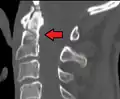

Type 3 odontoid fracture -

Type 2 dens fracture